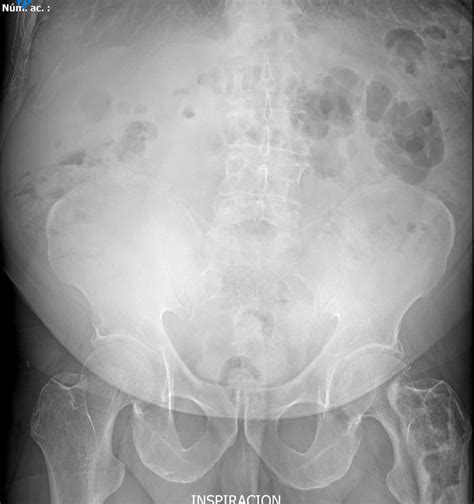

Common Findings in a Normal Abdominal X Ray

A Normal Abdominal X Ray typically reveals the following structures and patterns:

• Gas patterns in the stomach and intestines

• Clear outlines of the liver, spleen, and kidneys

• No signs of obstruction or perforation

• No evidence of foreign bodies

These findings indicate that the abdominal organs are functioning normally and there are no immediate concerns.